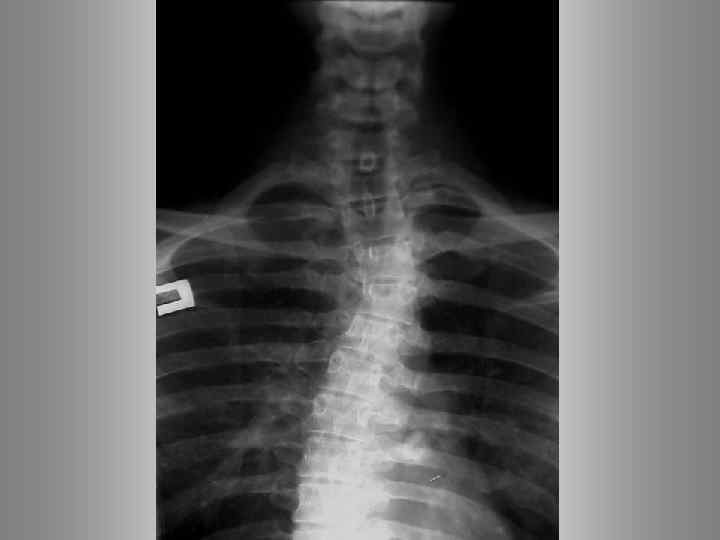

Опухоль. Метастаз. Остеопороз. Спондилит (дисцит)